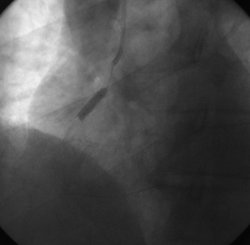

Cinecoronariografia: procedimento realizado por acesso radial direito com introdutor 6F, sendo evidenciado: origem anômala com tronco único emergindo do seio coronária direito. Artéria coronária direita (CD) dominante apresentando lesão obstrutiva severa no terço proximal com imagem de trombo (fluxo TIMI 3) (imagens 1 e 2). Tronco da coronária esquerda (TCE) longo e de bom calibre, com origem no tronco coronário único. Artéria circunflexa (Cx) e ramos marginais com irregularidades parietais discretas, sem lesões obstrutivas. Artéria descendente anterior (DA) e ramos diagonais com irregularidades parietais discretas, sem lesões obstrutivas (imagens 3 e 4). Ventrículo esquerdo (VE) com hipocinesia inferior importante.

Intervenção Coronária Percutânea: posicionado cateter terapêutico JR 6F 4,0 e cateterizada a artéria coronária direita. Progredido fio-guia 0,014“ Galeo (Biotronik) na artéria CD. Realizada angioplastia com implante direto de um stent não farmacológico Prokinetic Energy (Biotronik) 3,5 x 26 mm (16 atm) com sucesso. Procedimento otimizado com pós-dilatação com balão NC Sprinter (Medtronic) 4,5 x 12 mm (20 atm) (imagens 5 e 6). Ao final do procedimento, artéria aberta com fluxo TIMI 3 (imagem 7).